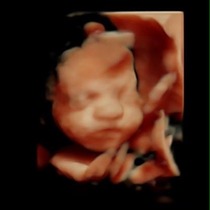

Went for a 4d scan today and got some fantastic piccies of my baby girl .... Heres sone for those not on fb.

June 2015 - bumps ahoy!

Ahh jazzy they are lovely...... Grin

Thanks chook, we were amazed at the images we got, never had 1 before and would totally recommend it.

She did lots of baby checks aswell and gave us a weight and length estimate.